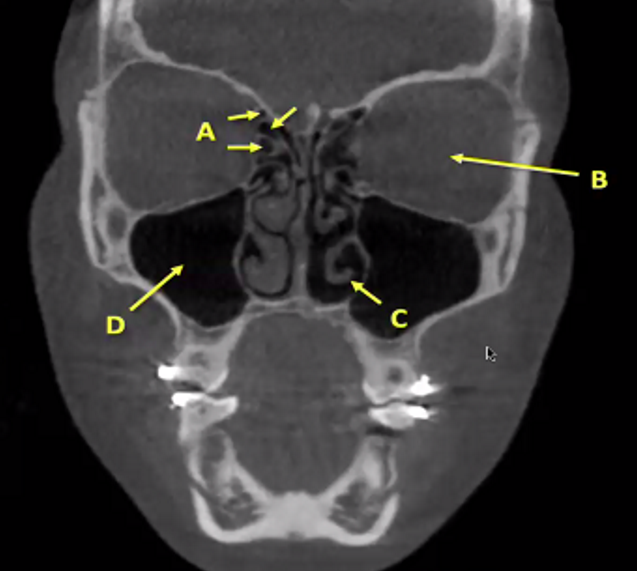

A

ethmoid sinuses

B

globe/eye

C

inferior concha

(meatus is the bone, here is inbetween so soft tissue)

D

Maxillary sinus